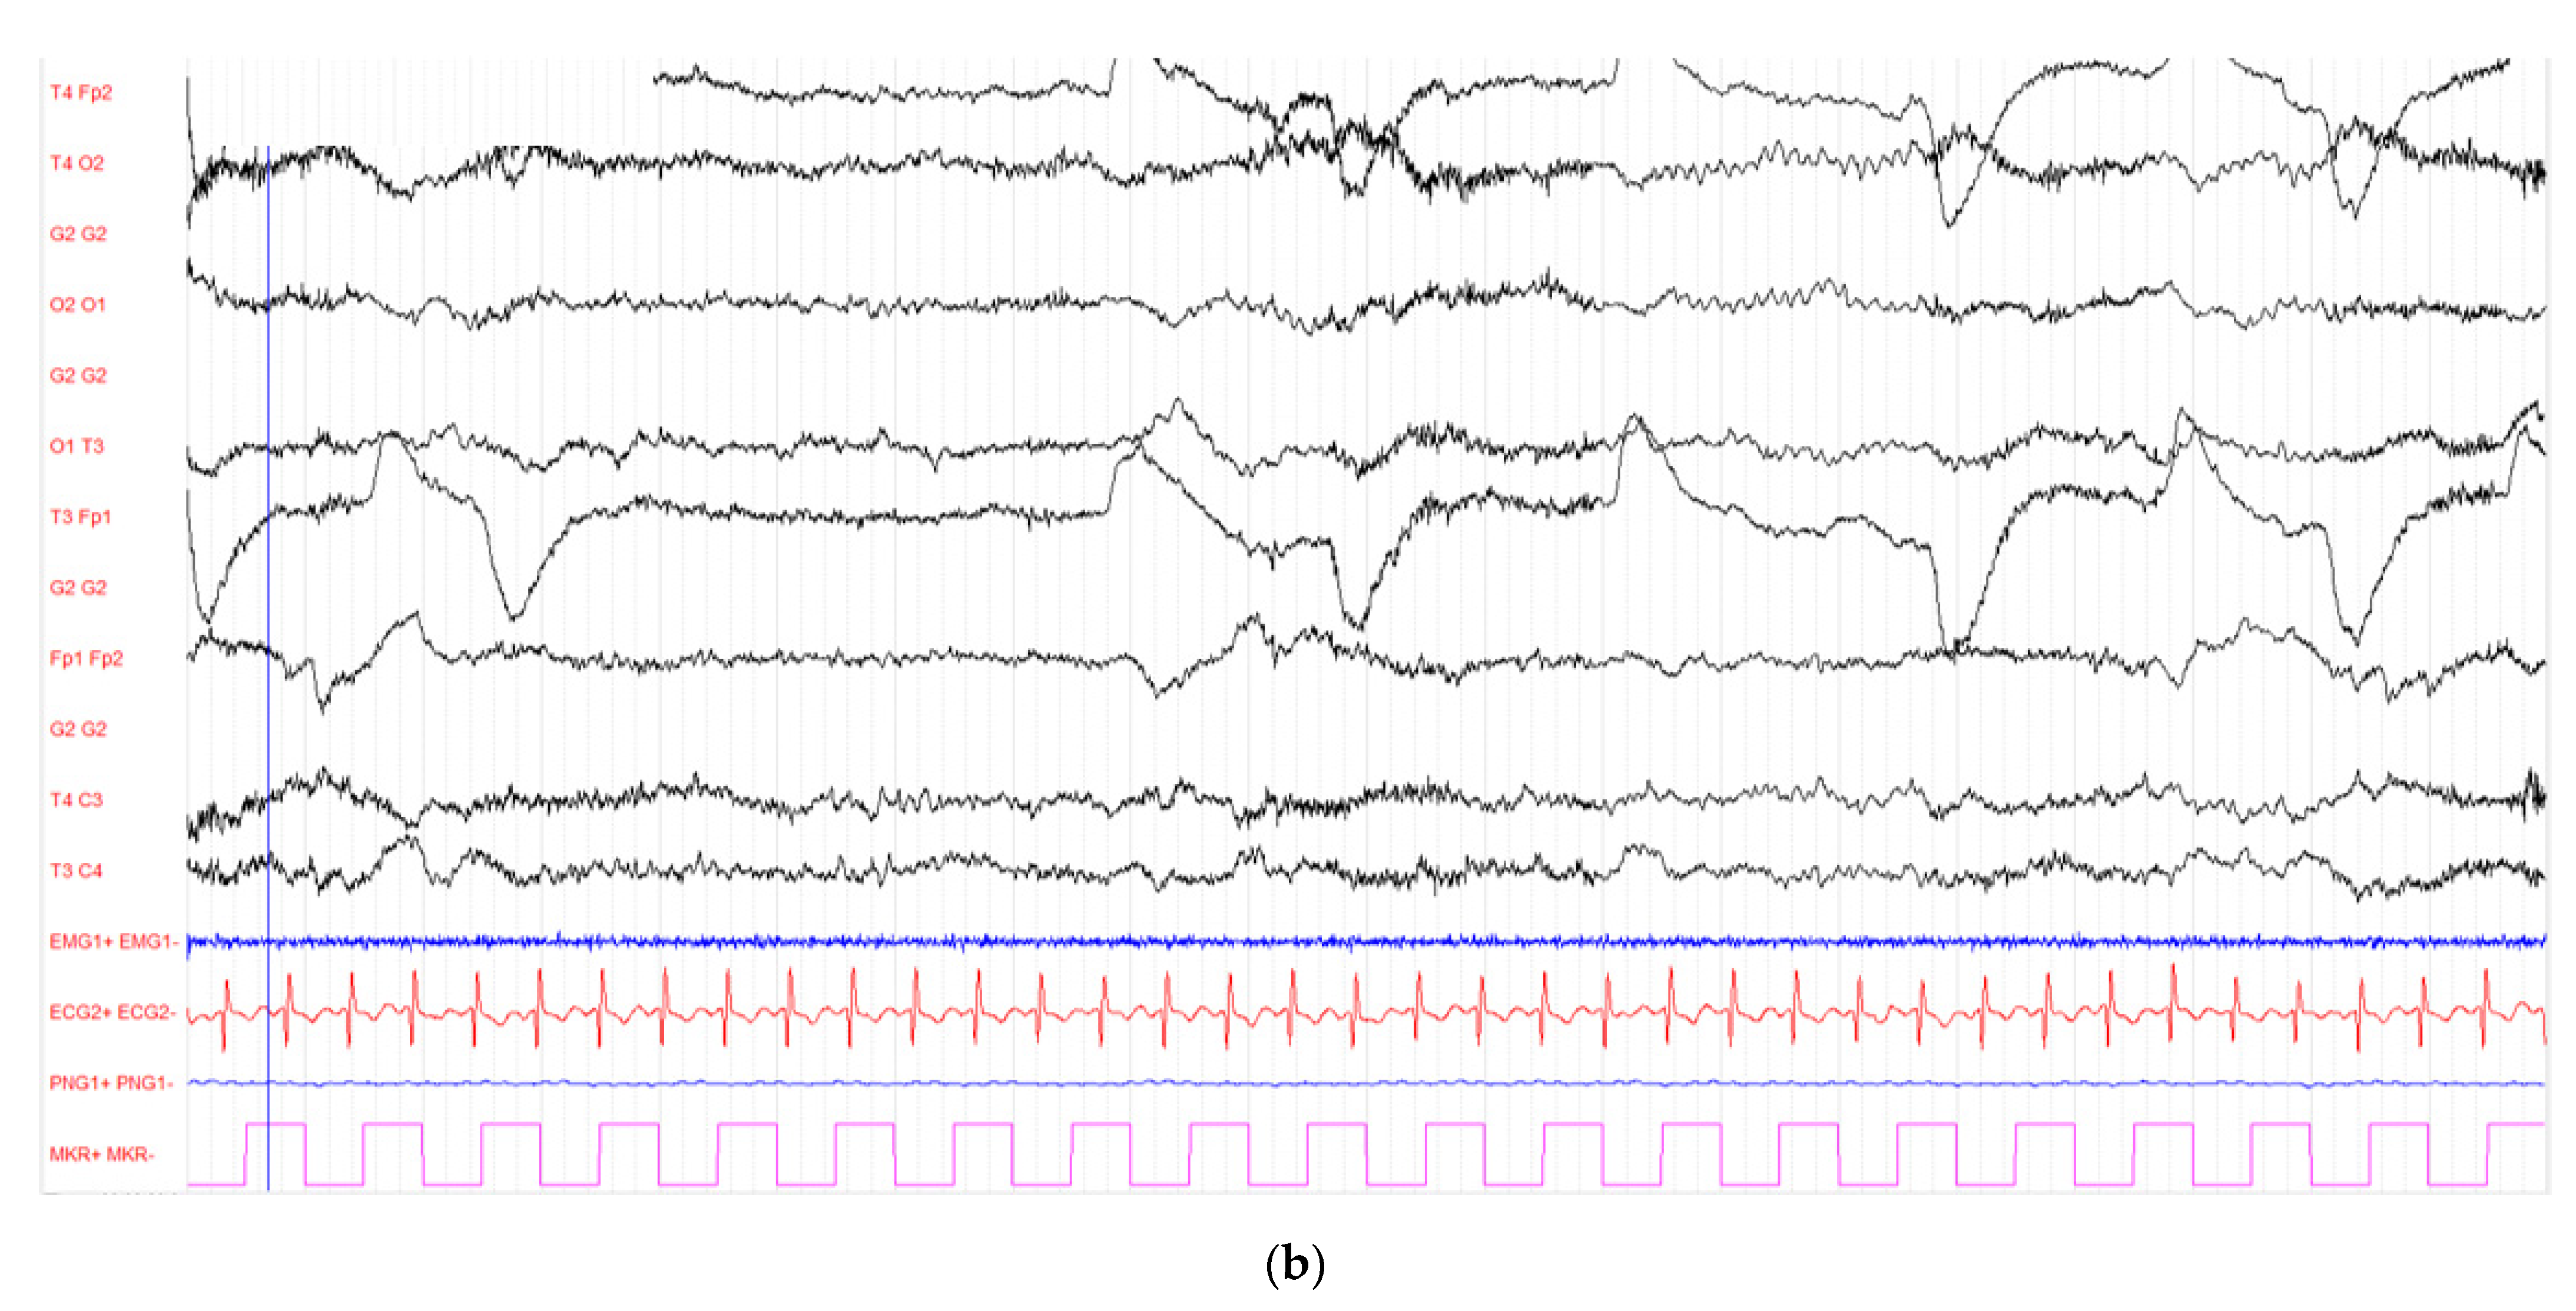

Brain MRI (Magnetic Resonance Imaging) slides are shown in Figure 2, Figure 3 and Figure 4. MR acquisitions were performed on an imaging machine (MRI) from General Electric, Milwaukee, WI, USA: Discovery MR 750w 3T. MRI data included a post-contrast (gadoterate meglumine, Dotarem, Guerbet, Villepinte, France) three-dimensional T1-weighted fast spoiled gradient recalled (FSPGR) acquisition (post-contrast 3DT1), post-contrast 3DT1, and fat-suppressed fluid attenuated inversion recovery (FLAIR) images. To ensure image quality, neuro-radiologists analyzed all the available imaging sequences. Table 1 details the MRI parameters machine. There were multiple bilateral subcortical, parietal, temporal, occipital and cerebellar T2 FLAIR high signals, predominantly in the posterior region with a slight right occipital cortex involvement but without translation in diffusion sequences. There were no abnormal T1 signals nor bleeding, but a left thalamic apparent diffusion coefficient (ADC) restriction was noted. On arterial spin labelling (ASL) perfusion sequences, there was an increased perfusion within the left temporo-parietal-occipital, left thalamic and right cerebellar regions; there was no thrombus on the TOF (time of flight) sequence. Laboratory evaluation for autoimmune, infectious and vascular secondary hypertension etiologies were found to be within normal limits.

Figure 4.

Initial brain Magnetic Resonance Imaging (MRI) with arterial spin labelling (ASL) sequences. (a,b) Supratentorial acquisitions, (c) Infratentorial acquisition. We observe an increased perfusion (represented from green to red) within the left temporo-parietal-occipital, left thalamic and right cerebellar regions.

As for the pathophysiology of PRES, the increase of the cerebral blood flow (CBF) on the ASL sequences in the left temporo-parietal-occipital and the left thalamic reflected the increased cerebral perfusion in response to the excessive metabolic demands secondary to the seizure activity. These changes can lead to vasogenic and/or cytotoxic edema. Furthermore, the left thalamic increased DWI signal and the reduced ADC value in the pulvinar region was related to the status epilepticus. Indeed, the thalamus is involved in the transfer of information between the cortical and subcortical structures of critical activities, and potentially in their regulation and propagation [22]. The contralateral cerebellar increased CBF was due to the crossed cortico-thalamo-rubro-dentato-cerebellar fascicles, also called the crossed cerebellar diaschisis, represented in Figure 7 [23,24].